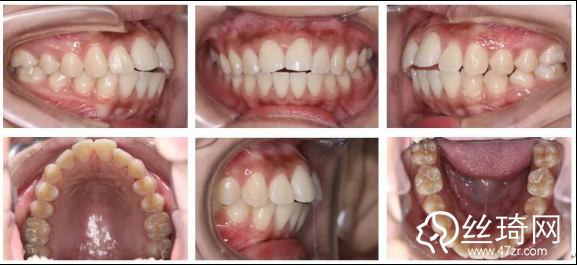

2.* 口內(nèi)檢查(以及調(diào)節(jié)前后口內(nèi)對比):

* 口內(nèi)檢查(以及調(diào)節(jié)前后口內(nèi)對比):

矯正后

上下牙列齊,前牙覆牙合覆蓋正常,中線正,雙側(cè)尖牙及磨牙關(guān)系中性,雙側(cè)后牙尖窩關(guān)系良好。

* 模型分析(以及調(diào)節(jié)前后模型對比):

矯正前

上牙列擁擠2.5 mm,下牙列擁擠1 mm;前牙開牙合2 mm,覆蓋4 mm;下中線左偏1.5 mm;Spee曲線深1.5 mm;前牙及全牙Bolton比基本正常。